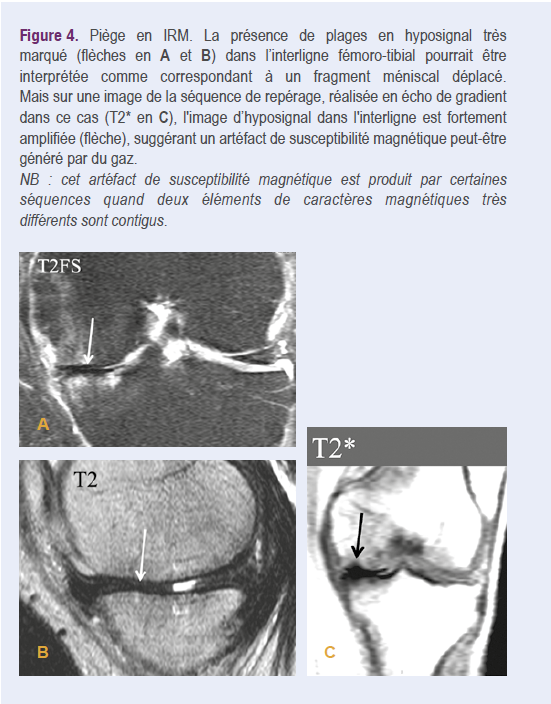

- dans le genou, un phénomène du vide -pas très fréquent- peut être observé essentiellement dans le compartiment fémoro tibial médial en décubitus (Figure 2c). Dans des articulations compartimentées comme le genou, un phénomène du vide unicompartimental n’exclut pas la présence d’un épanchement dans d’autres compartiments7. Ce vide dans l’interligne articulaire peut, en IRM, être interprété erronément comme fragment méniscal déplacé18,19. Ce piège peut être reconnu par l’aspect beaucoup plus grossier de cette plage sur des séquences en écho de gradient, en raison de l’artéfact de susceptibilité magnétique19. Il peut être utile dans ce cas de regarder les images des séquences de repérage, souvent réalisées en écho de gradient (Figure 4).

![]() |